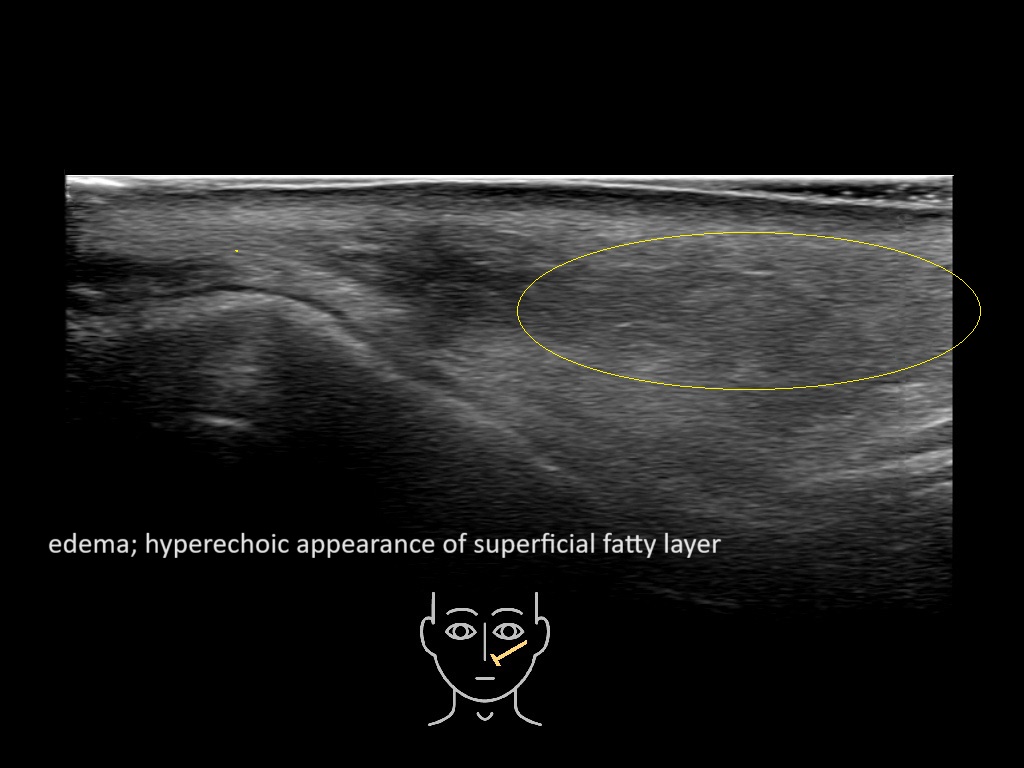

With ultrasound signs of inflammation can be visualized. Edema can be seen as a hyperechoic appearance of the subcutaneous fat, sometimes separated by hypoechoic fluid filled area’s, known as cobblestone appearance. Increased vascularization (hypervascularity) can be seen on colour Doppler. An abscess will appear as a fluid collection appearing as an irregular hypoechoic area with heterogeneous internal echoes and a thickened wall. Posterior acoustic enhancement can be present, and there is vascularity around but not within the mass. Under ultrasound guidance, abscesses can be managed by needle aspirations (18G) under antibiotic cover.